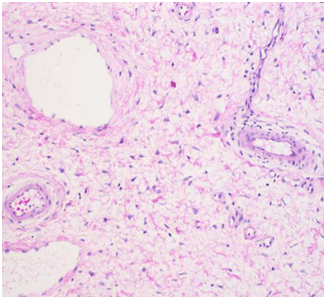

The soft tissue sonogram showed a mass measuring approximately 5.3 cm x 4.7 cm x 2.3 cm, which was projecting from a vascular stalk on the labial majora. The lesion was mildly heterogeneous in echotexture, appearing predominantly solid (Figure 3). The patient underwent wide local excision of the mass. Pathology of the mass showed an aggressive angiomyxoma. The pathologist also noted “this mesenchymal lesion is locally aggressive with a high risk for recurrence if incompletely excised. Although the pedicle margin of resection appears free of the lesional process further clinical concern may warrant conservative excision at the site of lesion attachment”. It was also noted that the mass was hypocellular and composed of stellate cells with an ill-defined cytoplasm distributed through a finely fibrillar and myxoid matrix. The nuclei were bland and mitoses were not present. There were numerous thin and thick walled blood vessels that blended with the surrounding matrix (Figures 5-8).

Figure 6 H&E stain showing thin and thick walled blood vessels with a finely fibrillar and myxoid matrix.